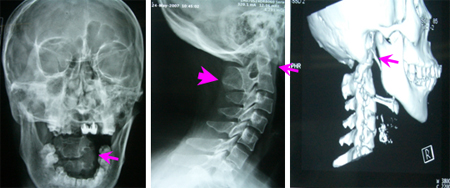

女性,43岁,头痛头晕3年,右上肢肌萎缩3月。查体:短颈、发髻低,颈部过伸、过屈位持续5分钟出现头痛头晕、右上肢麻木;右上肢肌萎缩,肌力4级,病理征阳性。影像学资料显示寰枢关节半脱位、颅底凹陷、颈2-3棘突分隔不全、小脑扁桃体下疝入椎管达C1-2水平(Chiari I 畸形)、脊髓空洞症。

专家评点:较全面的寰枕畸形会导致延颈髓腹背侧的压迫,从而引起相应的临床症状。治疗应在保证稳定性的前提下,尽量做到充分的延颈髓减压,手术可分为单纯颈前路内陷齿状突切除,单纯颈后路枕颈减压、侧块螺钉固定,或颈前路牵引复位、后路寰枕融合术。该患作了单纯颈后路的枕颈减压和枕大池成型术,术后临床症状即获充分改善,所以具体术式可根据患者首发症状和体征进行遴选。